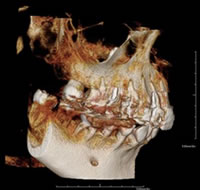

最新のCTレントゲンを導入しています。今まで見ることができない部分が立体的に、かつ詳細に確認できるので、正確な診断、緻密な治療計画の立案、安全で質の高い治療が可能です。

しかし、CTレントゲンは3D(立体的)での画像が得られ、従来の平面レントゲン画像に比べ、より豊富な情報を歯科医師に提供するレントゲンシステムです。

今まで見ることができない部分が立体的に、かつ詳細に確認できるので、正確な診断、緻密な治療計画の立案、安全で質の高い治療が可能です。

特に、インプラント治療において今やCT分析は必須です。顎骨の状態、神経、血管の走行など従来のレントゲンでは見ることのできない情報が安全性において特に重要です。当院では、より安全で精度の高い治療を提供しています。

歯科治療の説明というのは、患者さんにとって分かりにくいものですが、ご自身の顎の状態を3D画像でご覧いただき、イメージもしやすいので『分かりやすい、安心する』という声を多数頂いています。